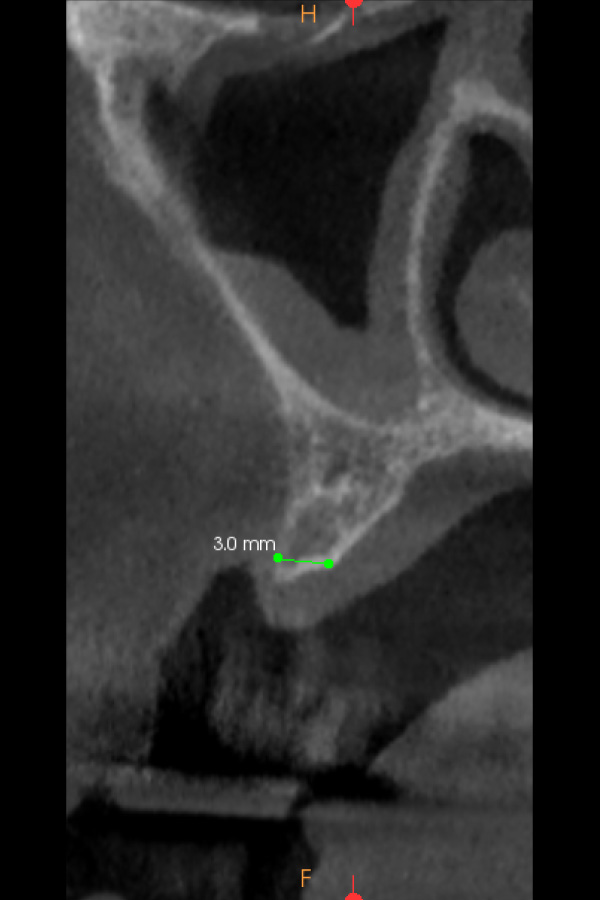

Figura 3, 4 y 5. Imágenes del CBCT en que se aprecia la poca disponibilidad ósea en sentido vestíbulo-palatino para la colocación de implantes dentales.